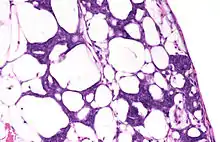

Leonard Betts, a cancer-eating mutant, creating a duplicate body. The effect required Toby Lindala to build a puppet with full-functioning mouth and eyes. | |

The show's design staff made extensive use of makeup to give McCrane the right look; applying all the makeup reportedly took "several hours".[9] McCrane's eyes were also augmented with specially-made contact lenses. Many of McCrane's scenes were physically exerting, such as the autopsy scene, which required McCrane to stick his head through a discreet hole in the set's mock dissection table. McCrane then held still, thereby giving the illusion that his head was severed and resting on the table. The scene in the bathtub required McCrane to spend several "long minutes" underwater motionless in full makeup.[9] The shot in which a new Betts emerges from the old one's mouth was created by Toby Lindala. Lindala intercut shots of McCrane with shots of a specially-designed puppet that had a full-functioning mouth and eyes. Laverne Basham and Lindala were later both nominated for an Emmy for Outstanding Makeup in a Series for their roles in this episode.[9]